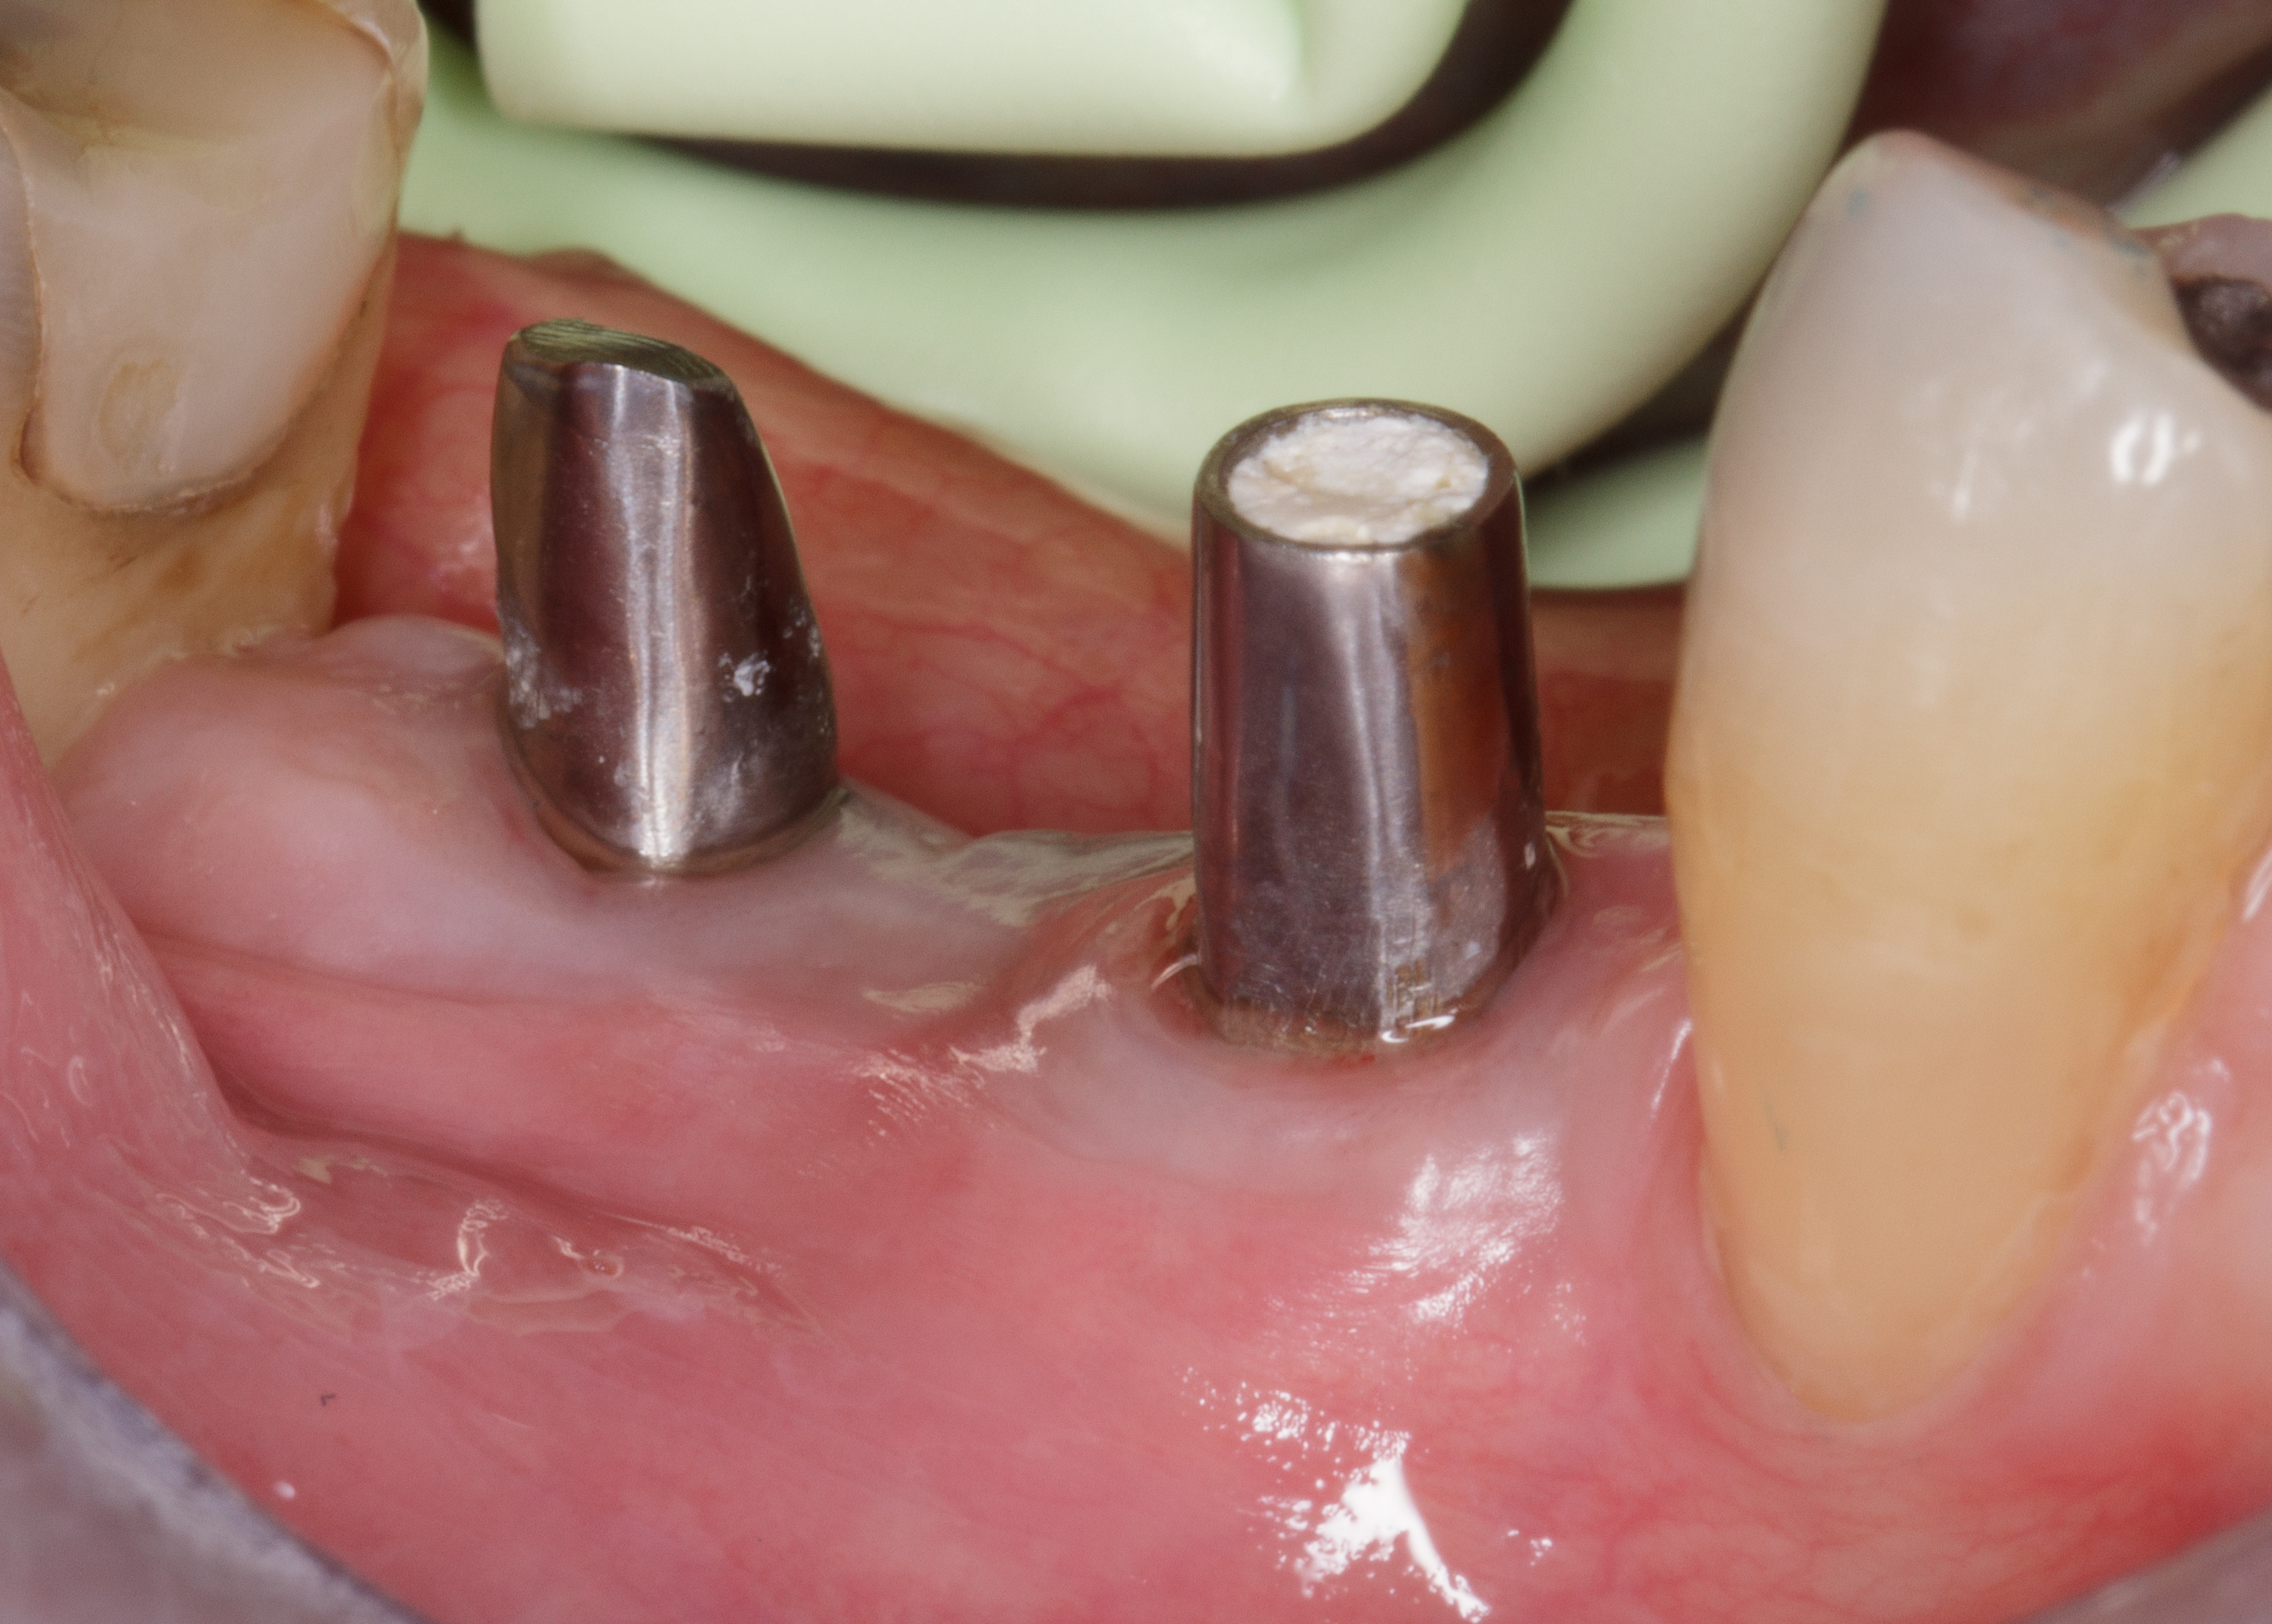

Il tunnel implantare è molto vascolarizzato. Viene inserito un impianto Neoss Tapered 4,5x11 mm, bone level, con torque di inserimento di 60 Ncm e ISQ 75 (Figure 20-22).

Dopo ulteriori quattro mesi si può procedere con l’ultima fase chirurgica di scopertura delle due fixture e di inserimento di abutment definitivi personalizzati.

Dopo l’apertura del lembo di accesso si evidenzia tessuto osseo corticalizzato anche nella zona vestibolare e crestale di 4.5. La visione occlusale consente di apprezzare la ricrescita ossea coronale alla vite tappo della fixture in 4.5 e del tessuto osseo vestibolare rispetto al bone housing. La misurazione ISQ di 4.5 restituisce l’alto valore di 86 (Figure 23-24).